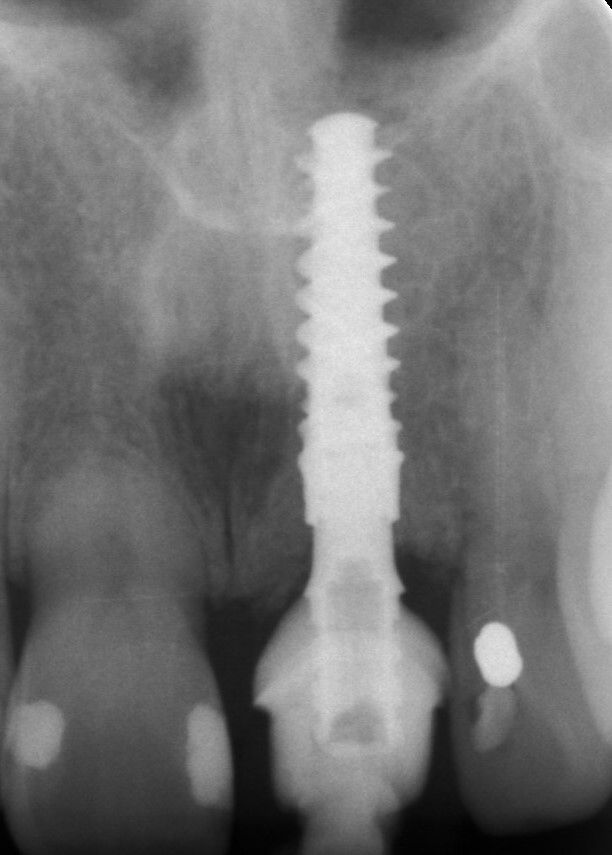

Женщина 53 лет обратилась в клинику по поводу сломанного центрального резца, который уже многократно восстанавливали керамической коронкой (Илл. 1, 2). По результатам сбора анамнеза и клинического осмотра стало ясно, что у пациентки хорошее состояние здоровья в целом и ротовой полости в частности, с хорошо сбалансированной окклюзией. Пациентка не курит. На конусно-лучевой компьютерной томограмме (КЛКТ) и периапикальной рентгенограмме стало очевидно, что у пациентки внешняя резорбция корня с очень небольшой ретенцией зуба в альвеолярной кости, из-за чего невозможно установить достаточный традиционный внутрикорневой штифт (Илл. 3,4).Учитывая то, что сломанный зуб находился в эстетически значимой зоне, пациентка попросила провести лечение максимально быстро и безопасно.

Так была установлена временная коронка без давления на мягкие ткани, при этом скорректировали режущий край таким образом, чтобы он не касался зубов антагонистов при экскурсии. Временная коронка была зафиксирована с усилием вращения 25 Нсм, после чего закрыли винтовую шахту и заполировали всю поверхность (Илл. 27). Через 7 дней состоялся контрольный осмотр, и была сделана периапикальная рентгенограмма (Илл. 28,29).